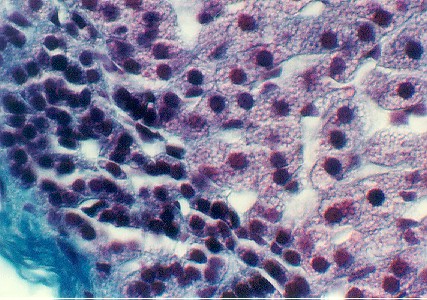

Look at your slide of the pancreas.  Find fields showing both acinar exocrine cells and patches of islet cells.  These patches are called the Islets of Langerhans.   They are the endocrine cells in the pancreas. Two major cell types include the alpha cell (reddish, producing glucagon) and the beta cell (bluish, producing insulin).   They may be easier to see in your slides, at higher magnification. What signal from the blood stream stimulates secretion from the beta cell?__________________________________.  What does it secrete?

What signal stimulates secretion from the alpha cell?  What is the function of glucagon?____________________________________________________

pancreas2.jpg (69626 bytes)

The above higher magnification shows a small islet surrounded by clusters of exocrine cells. You can see the purple and blue cells in the islet better.

What other hormone producing cells are found in the islet?